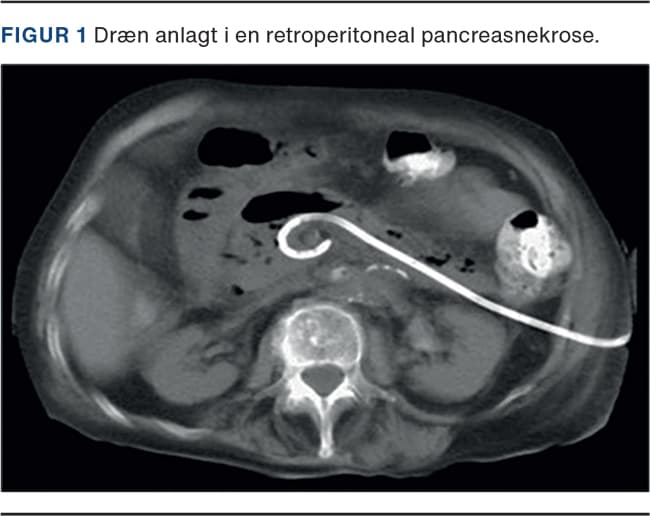

VARD forudgås af perkutan drænanlæggelse i den retroperitonealt beliggende pancreasnekrose (Figur 1) og foregår i generel anæstesi. Under proceduren ligger patienten i rygleje med enten venstre eller højre flanke eleveret afhængigt af nekrosens beliggenhed. Der foretages incision langs drænet, enten subkostalt eller interkostalt, hvorefter der dissekeres til den nekrotiske ansamling. Videoassisteret, med laparoskopisk optik, tømmes kaviteten for løst débris med sug og tænger (Figur 2 og Figur 3). Hvis forholdene tillader det, kan operationen foretages laparoskopisk ved anlæggelse af en gelport (Figur 4), hvorefter kaviteten kan åbnes med CO2-insufflation. Der kan herefter anvendes laparoskopiske instrumenter og foretages endoskopi gennem trokarer. Efter proceduren anlægges der to store skylle- eller bølgedræn i kaviteten mhp. sufficient postoperativ drænage og lavage.